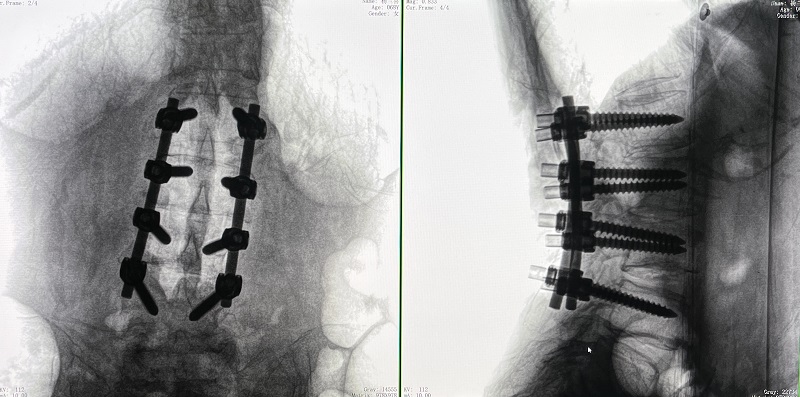

術(shù)后圖像